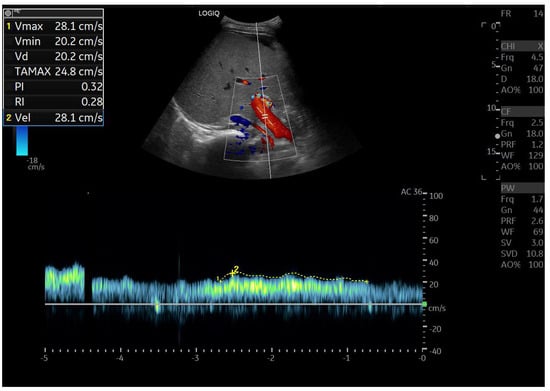

Doppler patterns in Fontan patients resemble those observed in chronic liver disease, including reduced portal flow velocity (mean flow velocity < 14 cm/s) [56]. The Fontan procedure inevitably alters hepatic venous waveforms on Doppler US (Figure 10, Figure 11, Figure 12 and Figure 13). Inverted portal flow has a specificity of 100% for diagnosing PHTN [57] (Figure 12). The hepatopetal phase pattern in the hepatic vein differs between patients with total cavo-pulmonary anastomosis (including both lateral tunnels and extracardiac conduits) and those with atrio–pulmonary connection [58,59,60]. In atrio–pulmonary connection, hepatopetal flow is preserved (Figure 10), reflecting the exclusion of atrial contribution to venous circulation, whereas in total cavo-pulmonary anastomosis, flow reversal (Figure 11) occurs only during early expiration. Similarly to congestive heart failure, hepatic veins and the IVC are dilated, with abnormally increased hepatic vein pulsatility, regardless of the anastomosis technique [54,61,62]. The loss of the normal three-phase Doppler pattern in hepatic veins is universal following bi-cavo-pulmonary surgery due to the absence of atrial contraction. The presence of a monophasic pattern indicates advanced liver injury [63].

Among individuals with Fontan physiology, the hepatic veins typically show a dampened, predominantly hepatopetal monophasic waveform, reflecting the presence of long-standing hepatic congestion. Venous flow velocities are markedly reduced compared with those measured in healthy individuals [63,64]. In contrast, in later stages characterized by cirrhosis and increased hepatic stiffness, further dampening or paradoxical changes in the venous flow pattern may be observed [37,56,64].

In particular, the hepatic venous Doppler waveform offers valuable insight into hemodynamic changes over time. In the early post-Fontan period, in the absence of atrial contraction and before structural liver damage is evident, the hepatic venous flow may display a relatively blunted monophasic or biphasic waveform with reduced phasicity, reflecting the lack of pulsatility and elevated central venous pressure [37,56,64].

As FALD progresses, and especially in the setting of developing cirrhosis, the Doppler waveform may become more dampened or even flat, corresponding to the increasing stiffness of the hepatic parenchyma, reduced compliance of the vascular bed, and worsening portal hypertension [37,56,64]. Simultaneously, the hepatic veins may appear dilated in the early and mid-stages of disease due to chronic venous congestion, but may show reduced caliber in later stages as fibrosis progresses and vascular remodeling occurs [37,56,64].